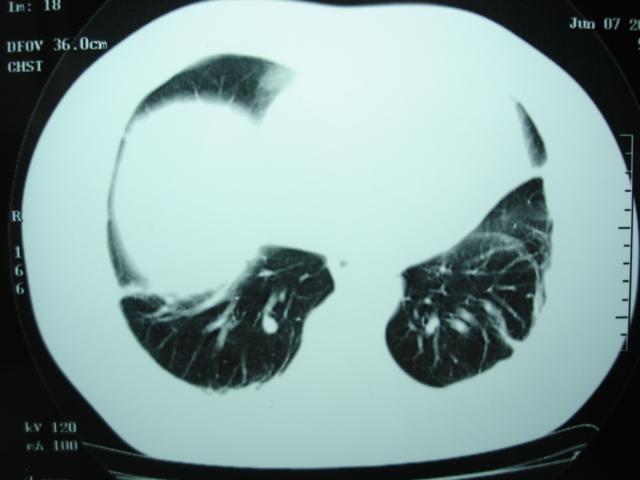

第一次ct2009.6.4

第二次ct2009.6.7 住院后ect未见异常,查痰(阴性)大量抗菌素抗炎一个月后病灶明显变小,7月5号出院后回家后口服抗菌素45天